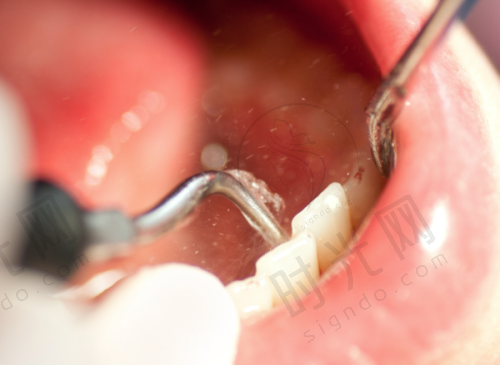

1. 牙周刮治:给牙齿“大扫除”,适合早期牙周炎松动

特别多人以为“洗牙”就能解决牙周问题,其实不然。我们平时洗牙(龈上洁治)只能清除牙齿表面的牙结石,而导致牙齿松动的“隐形杀手”——龈下牙结石(藏在牙龈沟里的结石),必须靠“牙周刮治”才能清除。牙周刮治就像“给牙齿做深度保洁”,医生用精细的器械深入牙龈下2 - 4毫米,刮除牙结石和感染的牙骨质,让牙龈重新贴合牙根,减少炎症对牙槽骨的破坏。

适合人群:一度松动、早期牙周炎(牙龈红肿出血、口臭)、正畸后清洁不到位导致的松动。比如前面提到的小林,通过龈上洁治 + 龈下刮治,配合局部上药(甲硝唑凝胶),2个月后牙齿松动基本消失。需要注意的是,牙周刮治后1 - 2周可能会有轻微敏感,这是正常现象,避免冷热刺激即可。